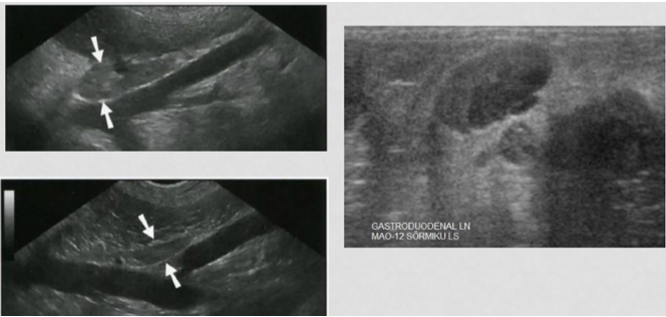

A

Lymph nodes